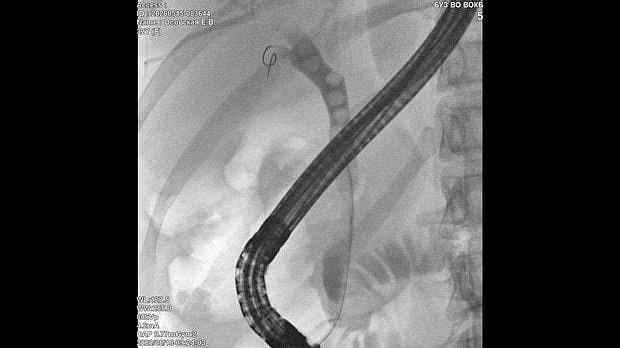

Здравствуйте. Пациентка, 32 года. Поступила на хирургическое отделение с диагнозом ЖКБ: холедохолитиаз. По данным МРТ: ЖКБ, множественные мелкие конкременты холедоха. При дуоденоскопии выявлено наличие вклиненного конкремента большого дуоденального сосочка. Выполнена прекатсфинктеротомия, получено 3 конкремента, диаметром около 0.4-0.5 см. Далее канюляция холедоха проволочным папиллотомом, выявлены многочисленные конкременты холедоха. Выполнена литоэкстракция ревизионным баллоном (на последнем фото окклюзионная холангиография - в просвете холедоха не конкременты, а пузырьки воздуха)).